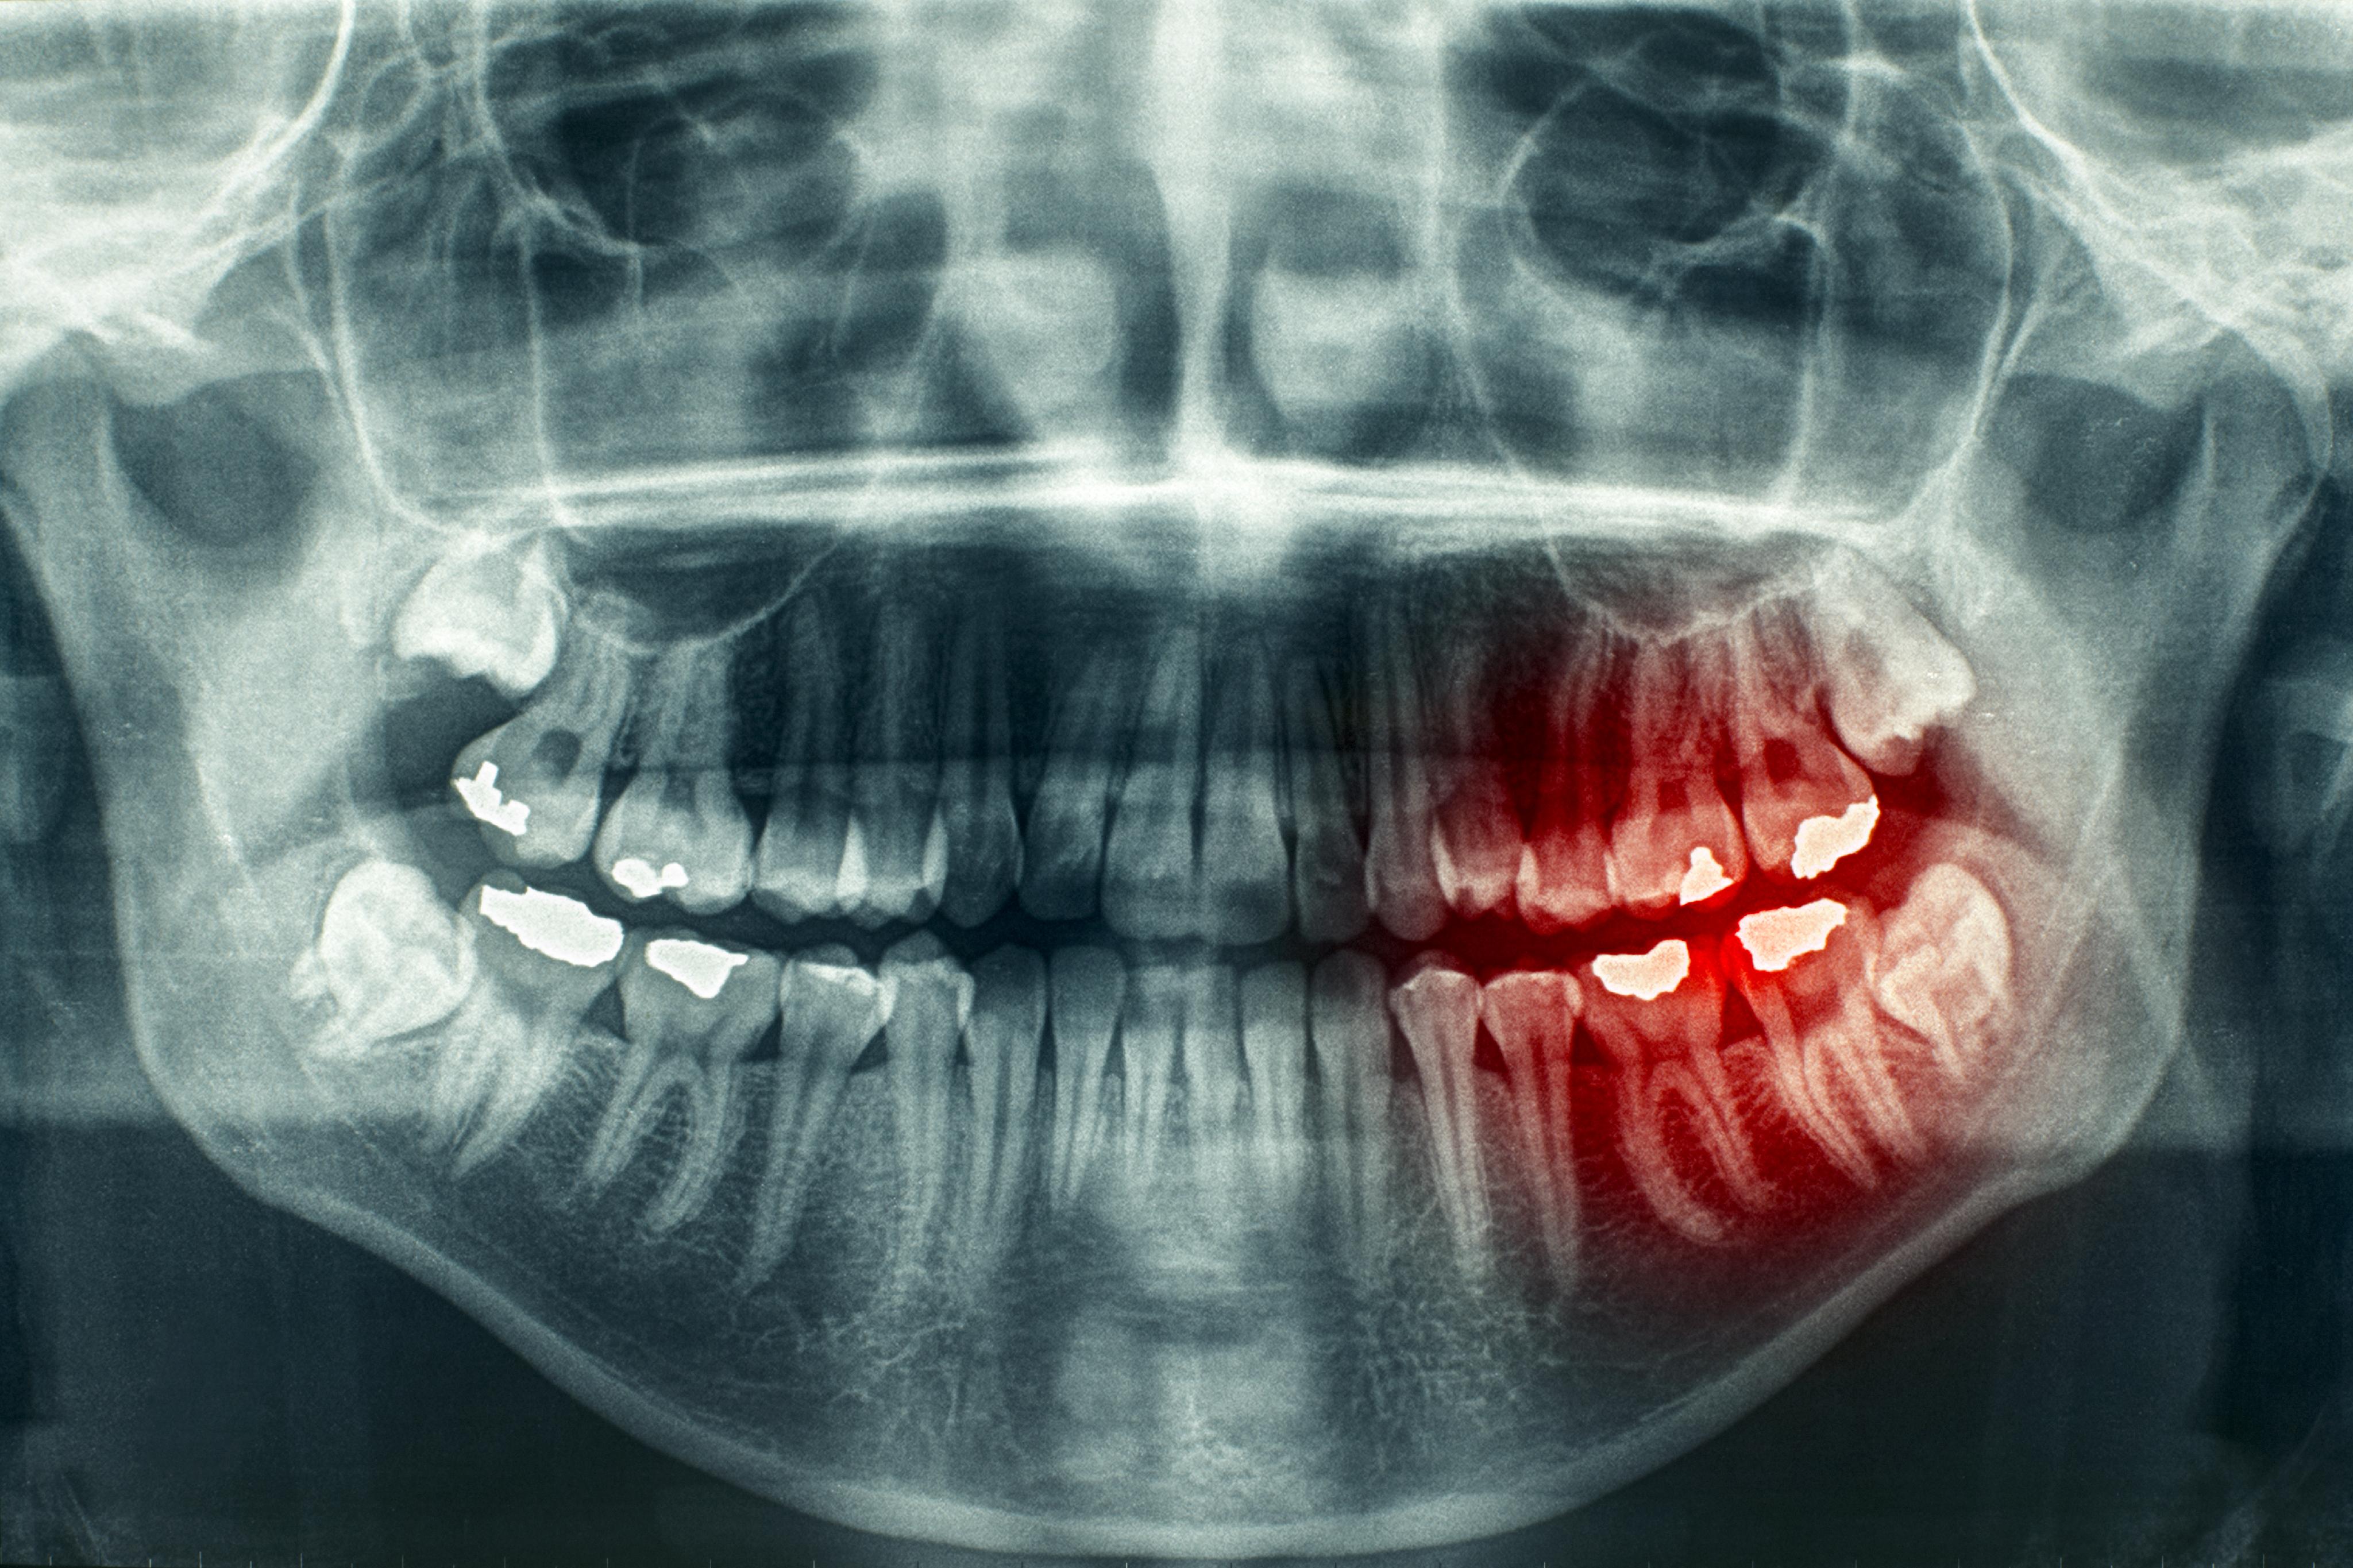

Примеры ортопантомограмм и их анатомия

Раздел: Фотоэссе